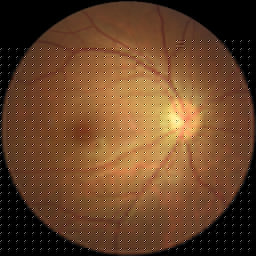

Diabétique retinopathy 99,29%Glaucoma 98,23%Cataract 99,87%.Normal 99,19%for 3200 images